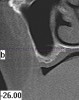

Figure 1  Computed tomography (CT) scan of the maxillary sinus and the bone available for implant placement in the upper molar region.

Figure 1

Figure 2  CT scan of the mandibular canal, relative to the expected location of implant placement. Inadequate bone in this region will address modification of the implant used, the need for osseous regeneration first, or in the most severe cases, possible contraindication for implant placement.

Figure 2

Figure 3  CT scan of the mandibular canal, relative to the expected location of implant placement. Inadequate bone in this region will address modification of the implant used, the need for osseous regeneration first, or in the most severe cases, possible contraindication for implant placement.

Figure 3